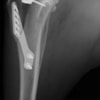

術後左後肢正面像

術前のTPAは左後肢33.1°右後肢26.8°でしたがTPLO実施により左後肢5.5°右後肢12°に矯正されました。

手術は片足ずつ行い、両膝とも術中の関節鏡検査にて前十字靭帯の完全断裂と半月板損傷を確認しました。TPLO、半月板切除と滑車溝形成を始めとした膝蓋骨脱臼整復術を実施いたしました。膝蓋骨の安定化を測るために外側支帯を強固に縫合し、内側支帯は切除し縫合せずに開放状態にしています。

術後の歩行状態は良好です。